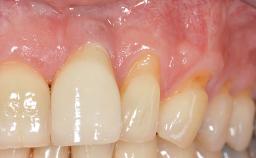

A 30-year-old woman was referred by her general dentist for evaluation of an esthetic complication related to previous implant treatment for congenitally missing maxillary lateral incisors. The patient’s chief complaint was the inadequate esthetic appearance of her smile. The case demonstrates the use of a combined approach to achieve optimal results. Two different flap designs - a tunnel technique and a coronally advanced flap - are employed based on the surgical objectives for the affected site.

Soft Tissue Anatomy Intact Defective

Soft Tissue Contour and Volume Slightly compromised